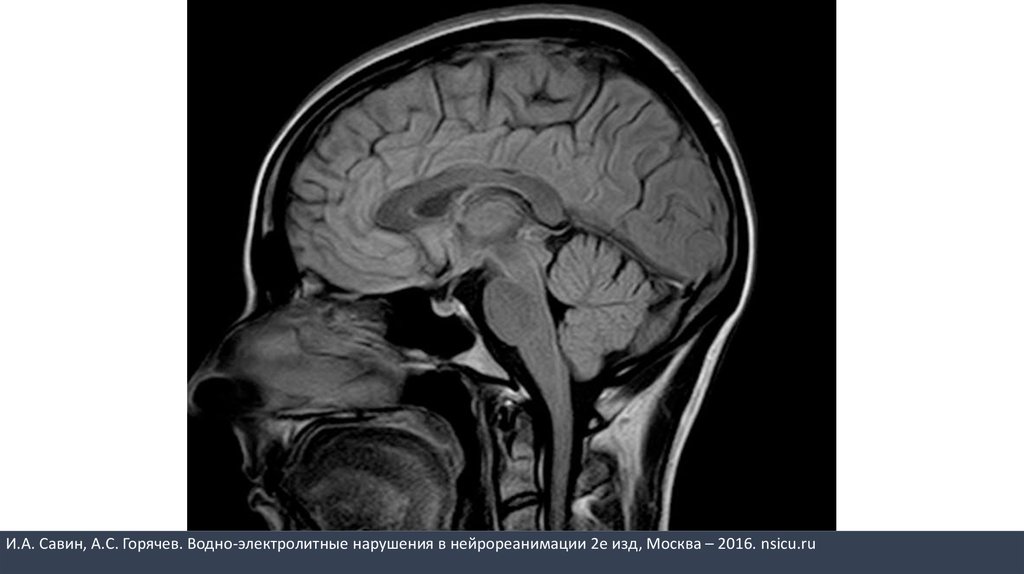

И.А. Савин, А.С. Горячев. Водно-электролитные нарушения в нейрореанимации 2е изд, Москва – 2016. nsicu.ru